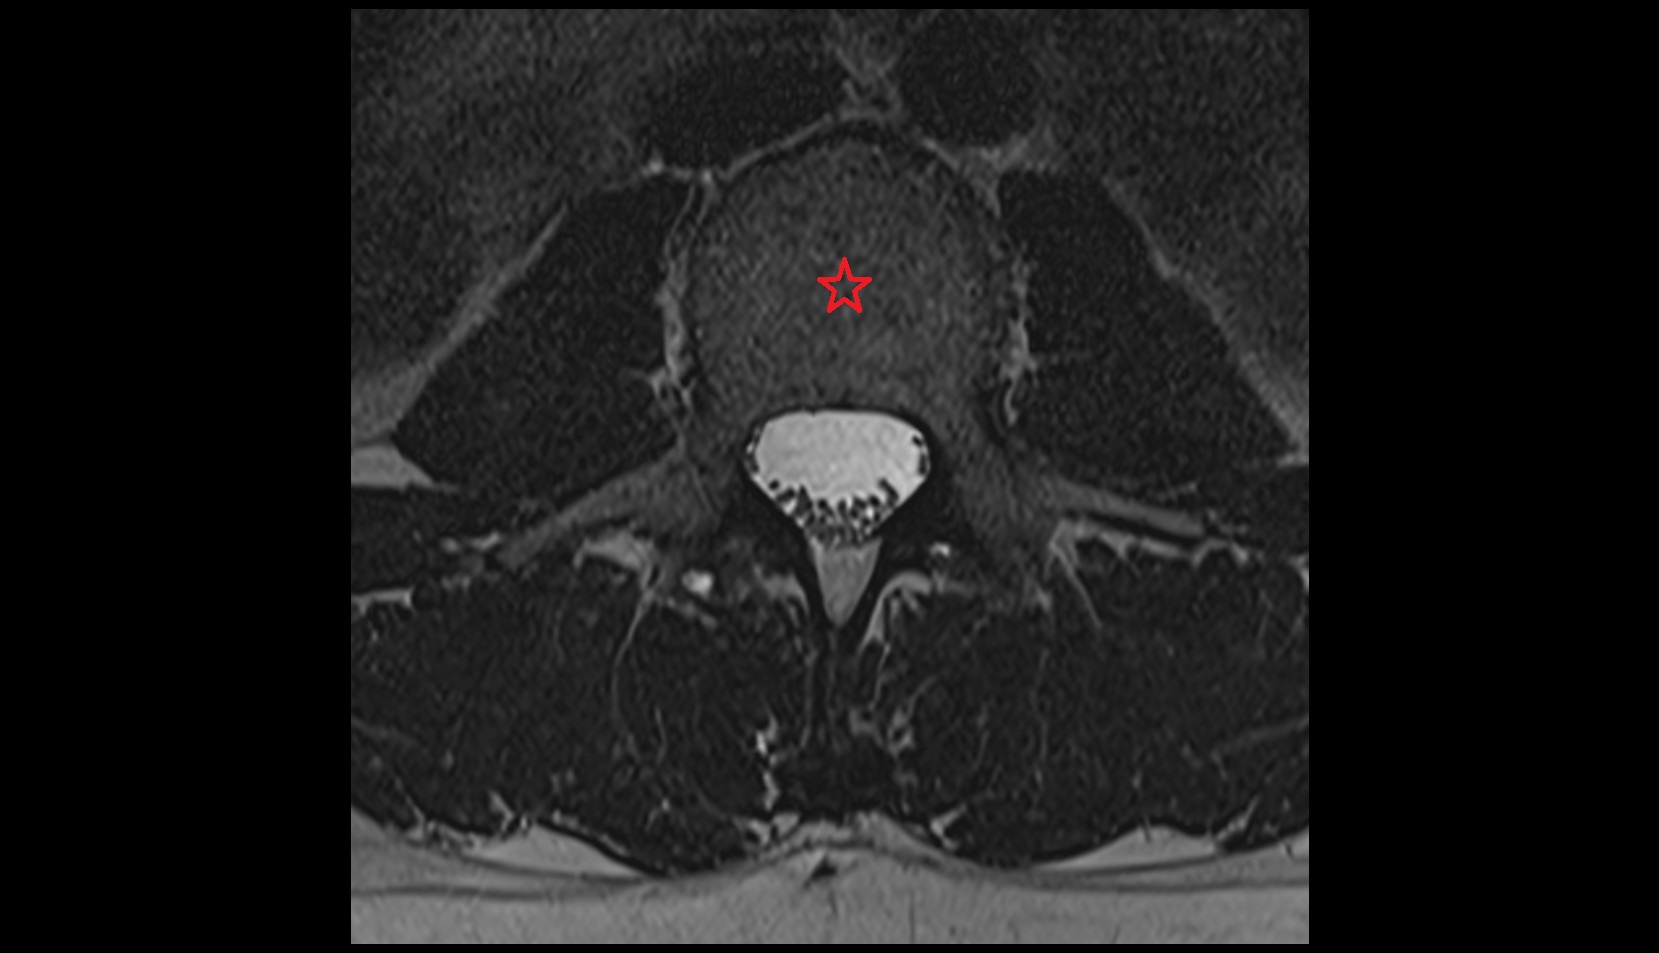

- Spinal dura mater

- Spinal epidural space

- subarachnoid space of spinal cord